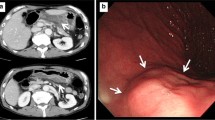

A case of phlegmonous gastritis, diagnosed for the first time without laparotomy and with spontaneous recovery, is described. The only procedure allowing nonsurgical diagnosis of this disease is endoscopic snare (“jumbo”) biopsy of the giant folds in the diseased parts of the stomach. Snare biopsy includes submucosal tissue which is the main site of histological changes in phlegmonous gastritis.